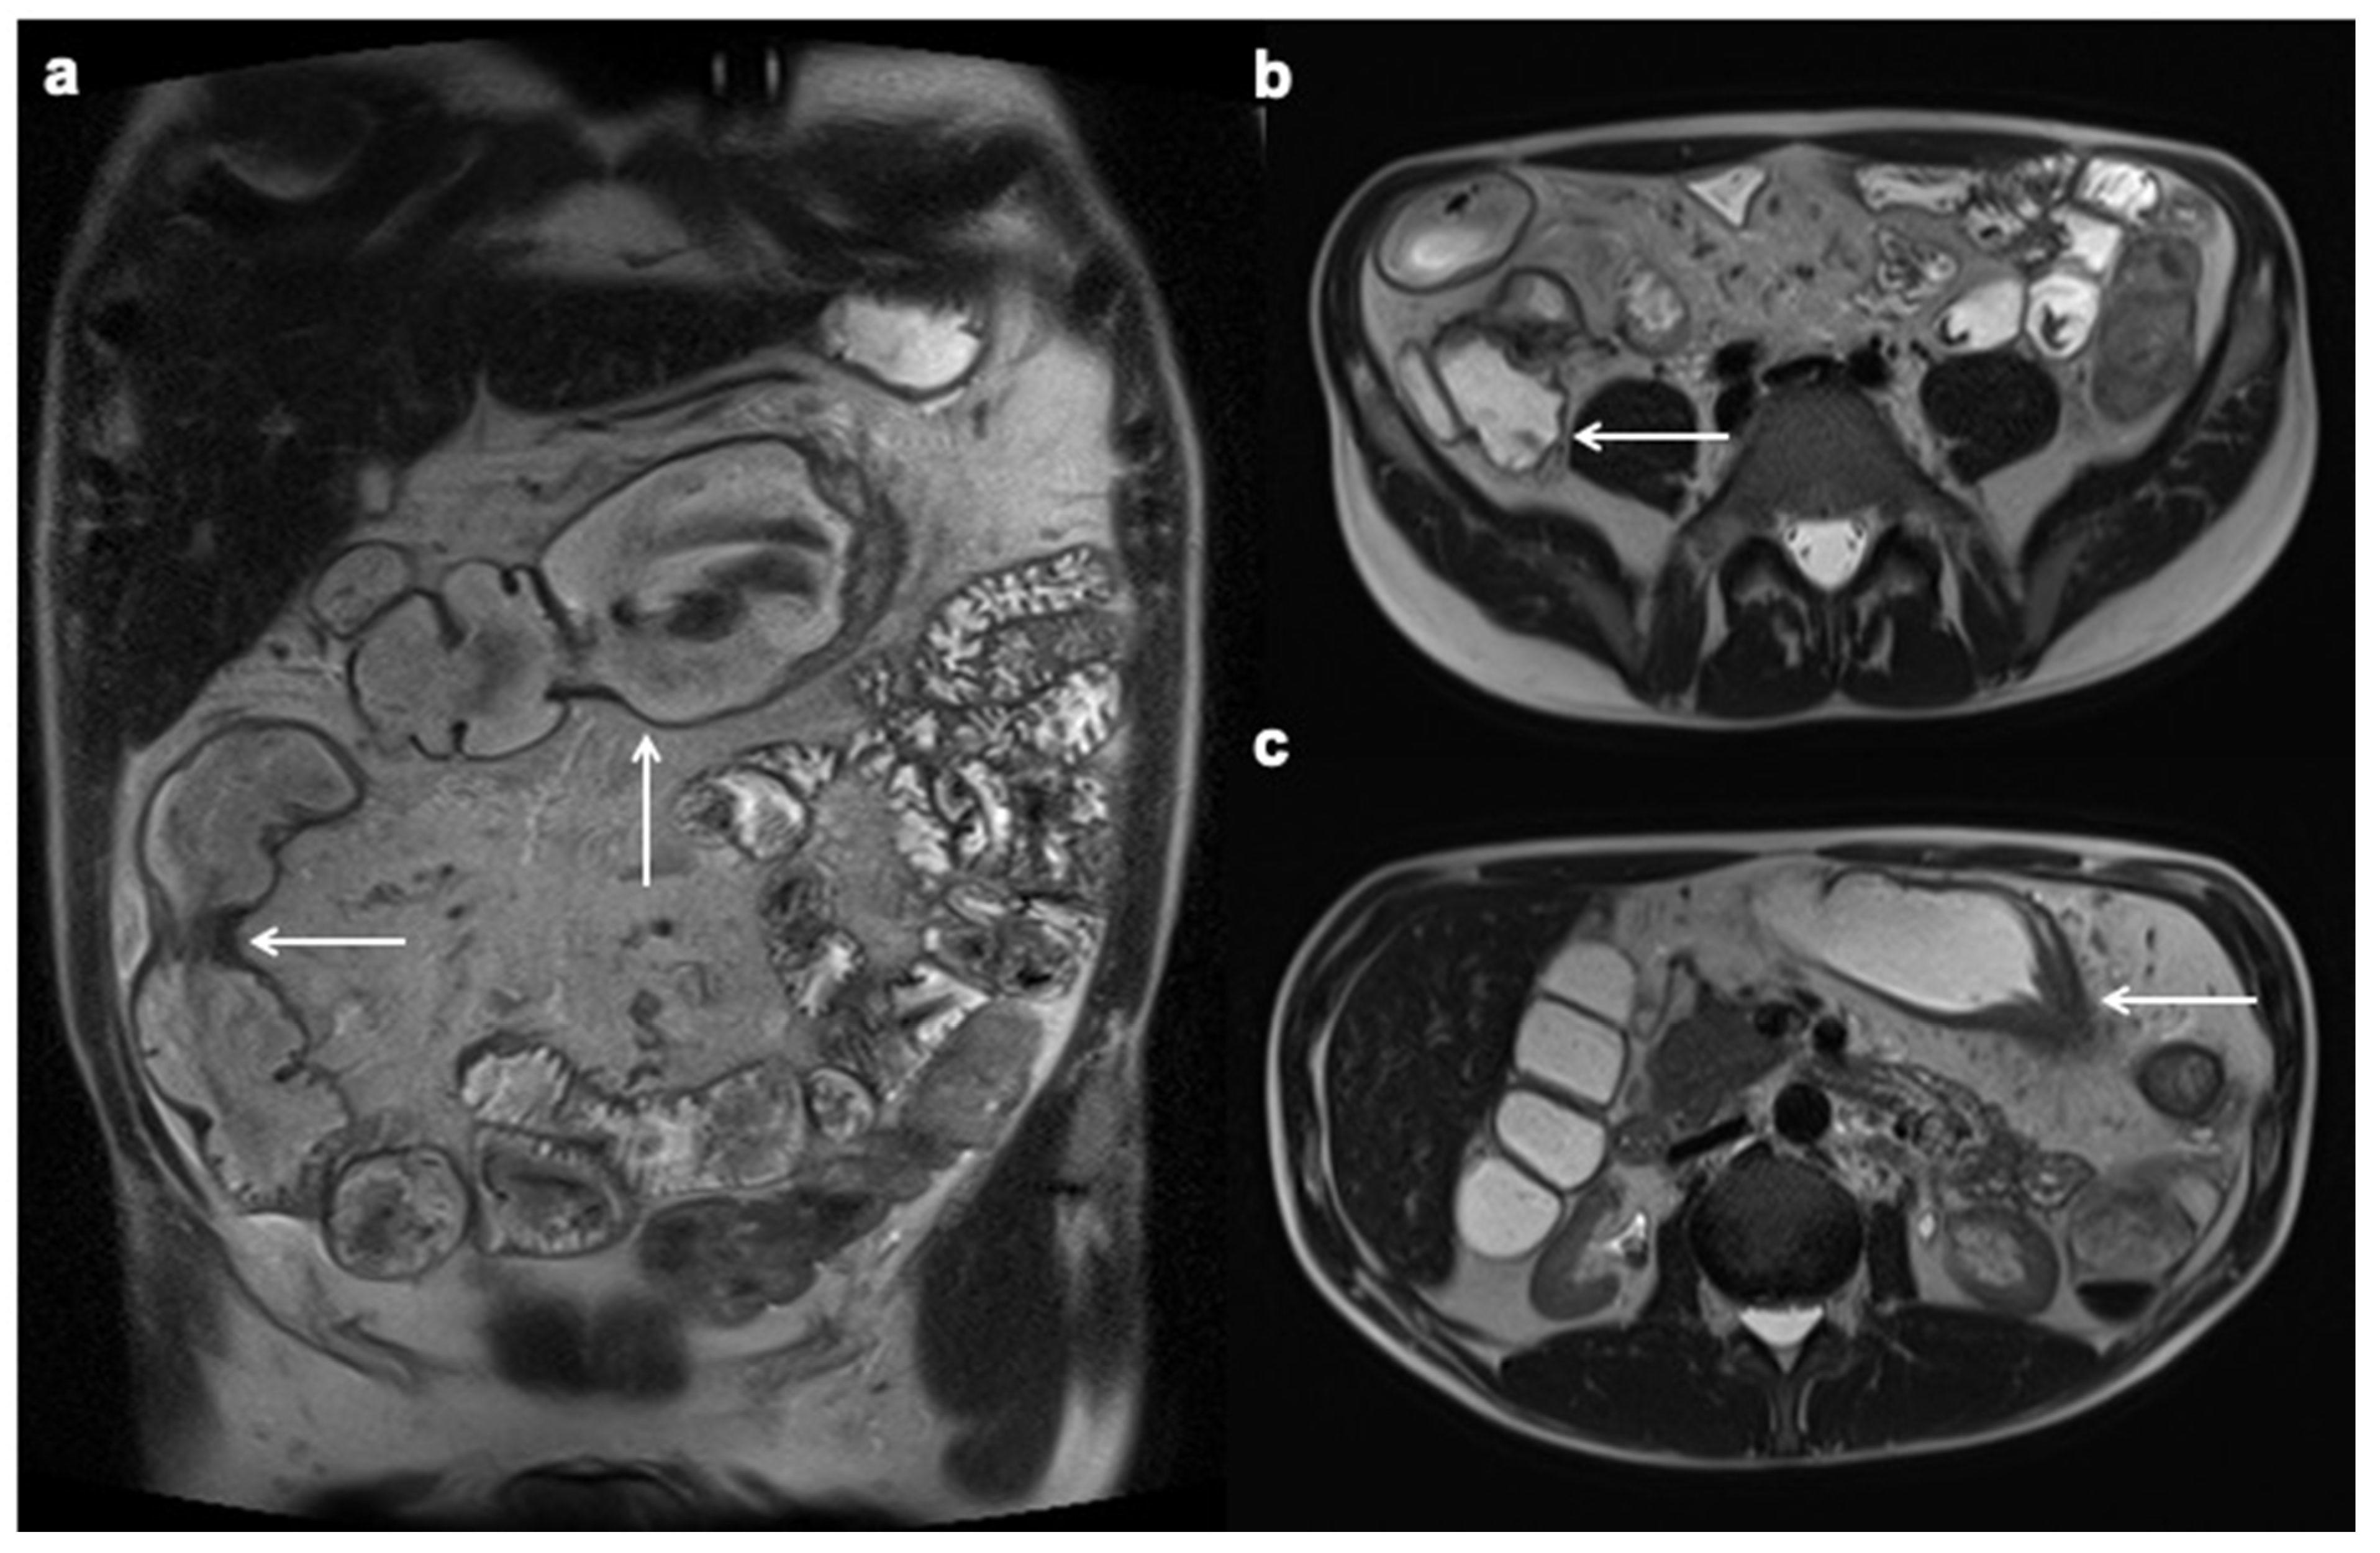

11. Imaging Findings Associated with Penetrating CD Inflammation and Complications

- Kelly, J.K.; Preshaw, R.M. Origin of fistulas in Crohn’s disease. J. Clin. Gastroenterol. 1989, 11, 193–196. [Google Scholar] [CrossRef]

- Oberhuber, G.; Stangl, P.C.; Vogelsang, H.; Schober, E.; Herbst, F.; Gasche, C. Significant association of strictures and internal fistula formation in Crohn’s disease. Virchows Arch. 2000, 437, 293–297. [Google Scholar] [CrossRef] [PubMed]

- Orscheln, E.S.; Dillman, J.R.; Towbin, A.J.; Denson, L.A.; Trout, A.T. Penetrating Crohn disease: Does it occur in the absence of stricturing disease? Abdom. Radiol. 2018, 43, 1583–1589. [Google Scholar] [CrossRef] [PubMed]

- Bruining, D.H.; Siddiki, H.A.; Fletcher, J.G.; Tremaine, W.J.; Sandborn, W.J.; Loftus, E.V., Jr. Prevalence of penetrating disease and extraintestinal manifestations of Crohn’s disease detected with CT enterography. Inflamm. Bowel Dis. 2008, 14, 1701–1706. [Google Scholar] [CrossRef]

- Booya, F.; Akram, S.; Fletcher, J.G.; Huprich, J.E.; Johnson, C.D.; Fidler, J.L.; Barlow, J.M.; Solem, C.A.; Sandborn, W.J.; Loftus, E.V. CT enterography and fistulizing Crohn’s disease: Clinical benefit and radiographic findings. Gastrointest. Radiol. 2008, 34, 467–475. [Google Scholar] [CrossRef] [PubMed]

- Vogel, J.; Moreira, A.D.L.; Baker, M.; Hammel, J.; Einstein, D.; Stocchi, L.; Fazio, V. CT Enterography for Crohn’s Disease: Accurate Preoperative Diagnostic Imaging. Dis. Colon Rectum 2007, 50, 1761–1769. [Google Scholar] [CrossRef]

- Oto, A.; Schmid-Tannwald, C.; Agrawal, G.; Kayhan, A.; Lakadamyali, H.; Orrin, S.; Sethi, I.; Sammet, S.; Fan, X. Diffusion-weighted MR imaging of abdominopelvic abscesses. Emerg. Radiol. 2011, 18, 515–524. [Google Scholar] [CrossRef]

- Schmid-Tannwald, C.; Agrawal, G.; Dahi, F.; Sethi, I.; Oto, A. Diffusion-weighted MRI: Role in detecting abdominopelvic internal fistulas and sinus tracts. J. Magn. Reson. Imaging 2011, 35, 125–131. [Google Scholar] [CrossRef]

- Barat, M.; Hoeffel, C.; Bouquot, M.; Jannot, A.S.; Dautry, R.; Boudiaf, M.; Pautrat, K.; Kaci, R.; Camus, M.; Eveno, C.; et al. Preoperative evaluation of small bowel complications in Crohn’s disease: Comparison of diffusion-weighted and contrast-enhanced MR imaging. Eur. Radiol. 2018, 29, 2034–2044. [Google Scholar] [CrossRef]